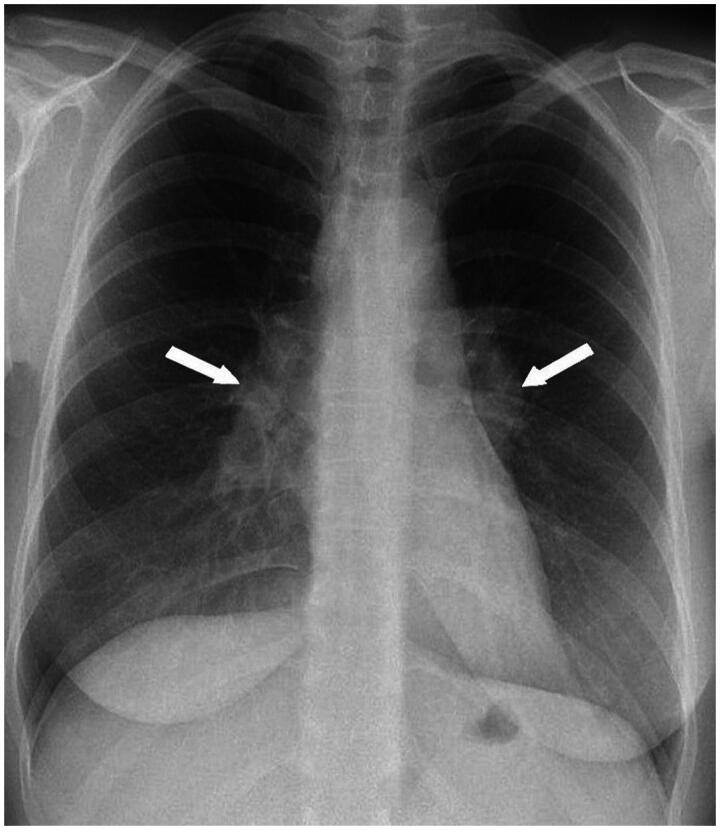

Background: Sarcoidosis is a chronic multisystem inflammatory disease of unknown aetiology, characterised by noncaseating granulomas and a variable clinical presentation. Despite its global distribution, sarcoidosis is relatively rare, with the highest prevalence in northern Europe. This poses challenges for primary care physicians due to its broad spectrum of symptoms, from organ-specific manifestations to general complaints like fatigue and concentration difficulties.